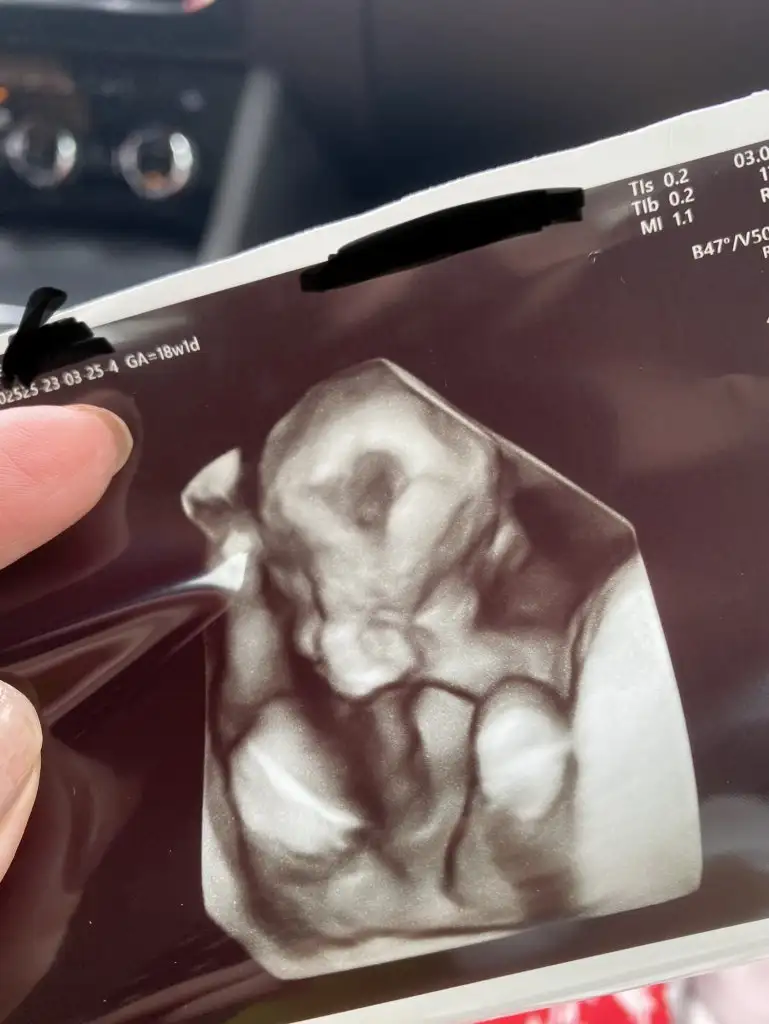

Teyzeleri, doktordan çıktık şimdi. Kızım çok utangaç olcak sanırım ellerini yüzünden hiç çekmedi. Doktor bir ara sarstı o ara sinirlenip çekti ellerini🙈 onun dışında her şey yolundaydı, boyu kilosu(220 gr🐣)